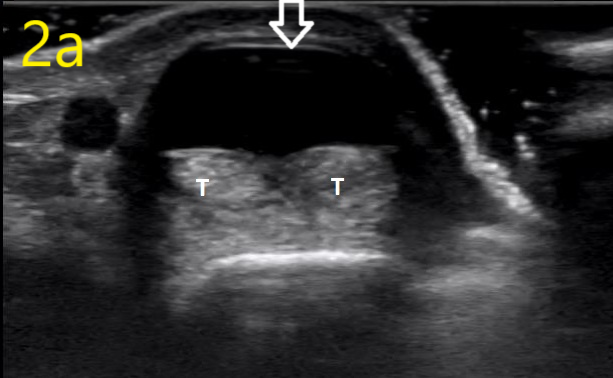

Image 2a

Ultrasound in Orthopedic Practice